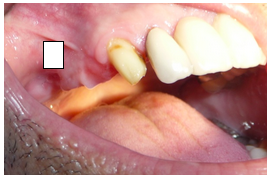

Paciente do sexo masculino, 58 anos se apresentou à clínica com histórico de perda de elementos dentais superiores do lado direito (figura 1). Após análise foi requerida radiografia panorâmica (figura 2). Constatada a pouca disponibilidade óssea na região, devido a pneumatização do seio maxilar, foi indicada a realização de cirurgia de elevação de seio maxilar.